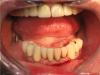

фима Опубликовано 25 октября, 2011 Поделиться Опубликовано 25 октября, 2011 Насколько я понял в верху съемник и его не трогали, в этом и вся радость.Да вот получилось и со своими зубами вверху. Отходила с двумя времянками . ОПГ показывал выше , добавляю фото. По порядку не грузится , но, я думаю, разберетесь.Нет фото верхней времянки - мне жаль. Ссылка на комментарий

pit Опубликовано 25 октября, 2011 Поделиться Опубликовано 25 октября, 2011 Спасибо за фотки, временные винты установлены параллельнее, чем постоянныеА фотографий окончательной работы у Вас нет? Ссылка на комментарий